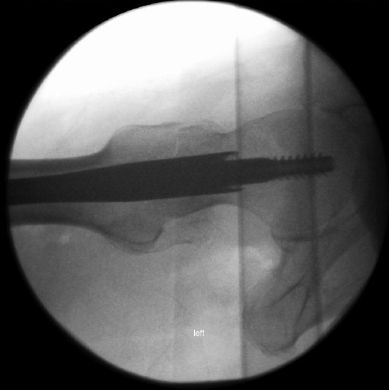

轴侧位:使股骨干、股骨颈和股骨头呈共线对齐,让术者能够观察到矢状面的细微复位不良。此外,植入物在股骨颈和股骨头内的放置情况可清晰显影。此体位最适用于将植入物定位到股骨头内,但股骨距区域显示不佳。应与标准侧位成像结合使用。

什么是c型臂术中透视骨科精读 | 股骨近端骨折的转子区域与矢状面力线术中透视技巧_https://www.jmylbn.com_新闻资讯_第7张

图7